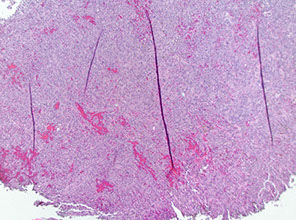

Giant cell arteritis of the breast. The vessel wall has been replaced by granulomatous inflammation. The process has compressed the vessel lumen to near-complete obstruction. A giant cell is shown in this field. B, Giant cell arteritis of the breast. Granulomatous inflammation and fibrinoid necrosis are shown within the wall of this vessel. C, Giant cell arteritis of the breast. The special elastin stain highlights the fragmentation of the internal elastic

lamina in this vessel (hematoxylin-eosin, original magnifications320 [A and B]; original magnification320 [C]).